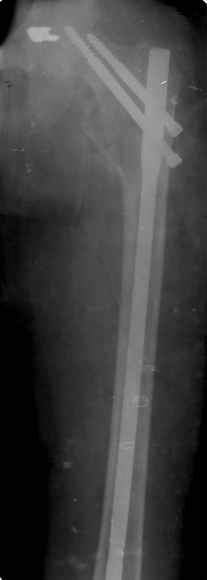

Спасибо за все ответы и комментарии по этому вопросу. Неделю назад мы прооперировали пациентку. Представляем ее снимки.